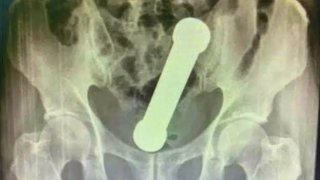

เรี่องราวที่กำลังเป็นไวรัล ในบราซิลตอนนี้ คือ เรื่องราวของชายบราซิล วัย 54 ปี ที่เอาดัมเบลที่มีหน้าตาคล้ายอวัยวะเพศชาย ซึ่งมีความยาว 20 เซนติเมตร และ กว้างประมาณ 5 เซนติเมตร ยัดเข้าไปในรูก้นของตัวเอง โดยหวังที่จะให้ตัวเองรู้สึกดีและมีความสุข แต่มันกลับผิดคาด เนื่องจากว่าดัมเบลมันผลุบ เข้าไปอยู่ข้างในแถมเอาออกไปได้อีก เขาเลยยอมจำนนโทรเรียกรถพยาบาลมารับ แล้วถูกเข็นไปมาในโรงพยาบาล ต่อหน้าประชาชี โดย.. ดูเพิ่ม

เล่นใหญ่ เอาไม่ออก ! เดือดร้อนหมอดึงออกให้ 🤣 ชายอายุ 54 ในบราซิลเข้ารักษาตัวในโรงพยาบาลหลังมีอาการปวดท้องถ่ายไม่ออกเพราะมีดัมเบลหนัก 2 กก.ยาว 20 ซม.อยู่ในทวาร จริงๆ มันติดอยู่ในนั้นมาสองวันแล้วเจ้าตัวพยายามเอาออกเองแต่ไม่สำเร็จ หมอต้องใช้มือล้วงเข้าไปเกือบสุดแขนเพื่อดึงมันออกมา มีหลายคนถามว่าทำเพื่ออะไร มันคือรสนิยมทางเพศค่ะเพราะในทวารหนักมันมีเส้นประสาทที่ไวต่อความรู้สึก กระตุ้นให้เกิดอารมณ์ทางเ.. ดูเพิ่ม